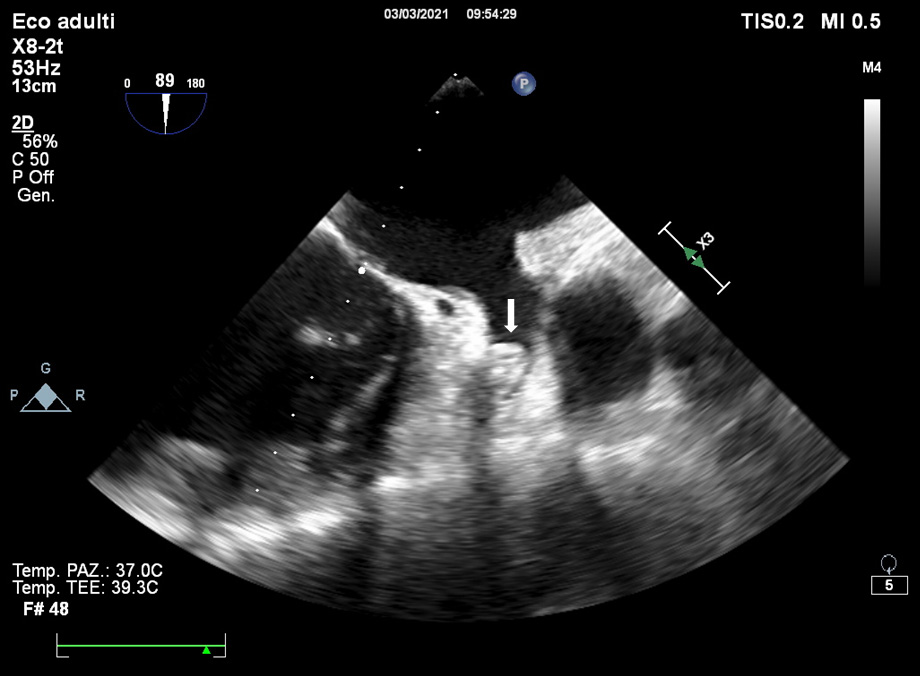

The main TOE e/o CCTA exclusion criterion is the existence of thrombus in the LAA [35]. Nowadays, TOE is the most used imaging technique to exclude the presence of thrombi in LAA (Fig. 3).

Fig. 3.The main TOE e/o CCTA exclusion criterion is the existence of thrombus in the LAA (see arrow).